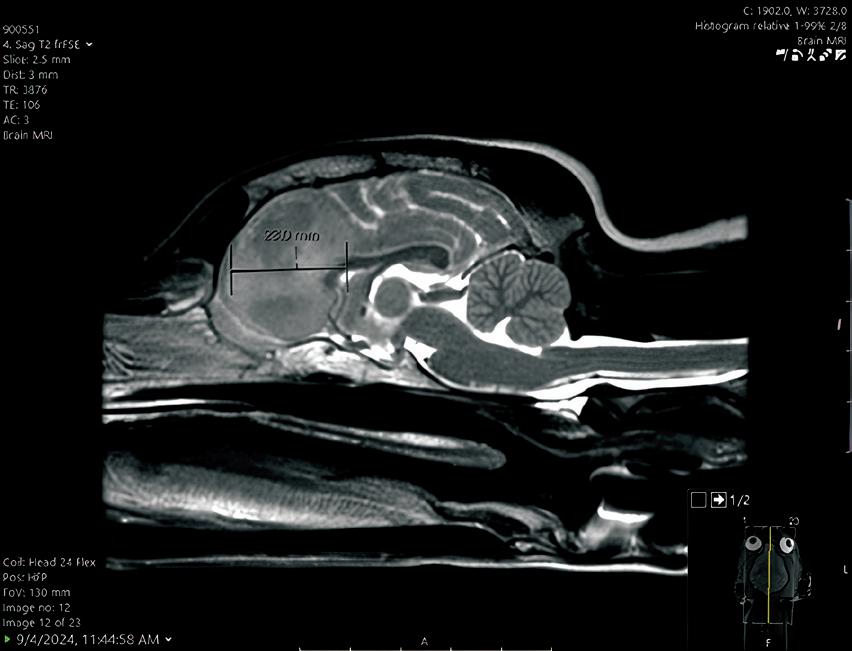

In August, Geddy Lee began having seizures, and her veterinarian referred the eight-year-old to Penn Vet for further evaluation. At Penn Vet’s Ryan Hospital, Tessa Arendt, DVM, specialty intern in neurology, and Wojciech Panek, DVM, DACVIM, assistant professor of neurology and neurosurgery in the Department of Clinical Sciences and Advanced Medicine, performed a brain MRI, which revealed a right frontal lobe mass.

“An MRI doesn’t always tell us exactly what we’re dealing with even though it allows us to see the tumor,” said Panek. “Based on Geddy Lee’s tumor imaging characteristics, we suspected a glioma—an aggressive brain tumor.”

“The technology created a hologram from Geddy Lee’s initial MRI, which was really helpful for procedure planning and navigating hard-to-see areas,” said Panek. By superimposing Geddy Lee’s MRI images with anatomical accuracy onto the dog’s skull, the surgeons were able to first biopsy and then debulk the tumor.